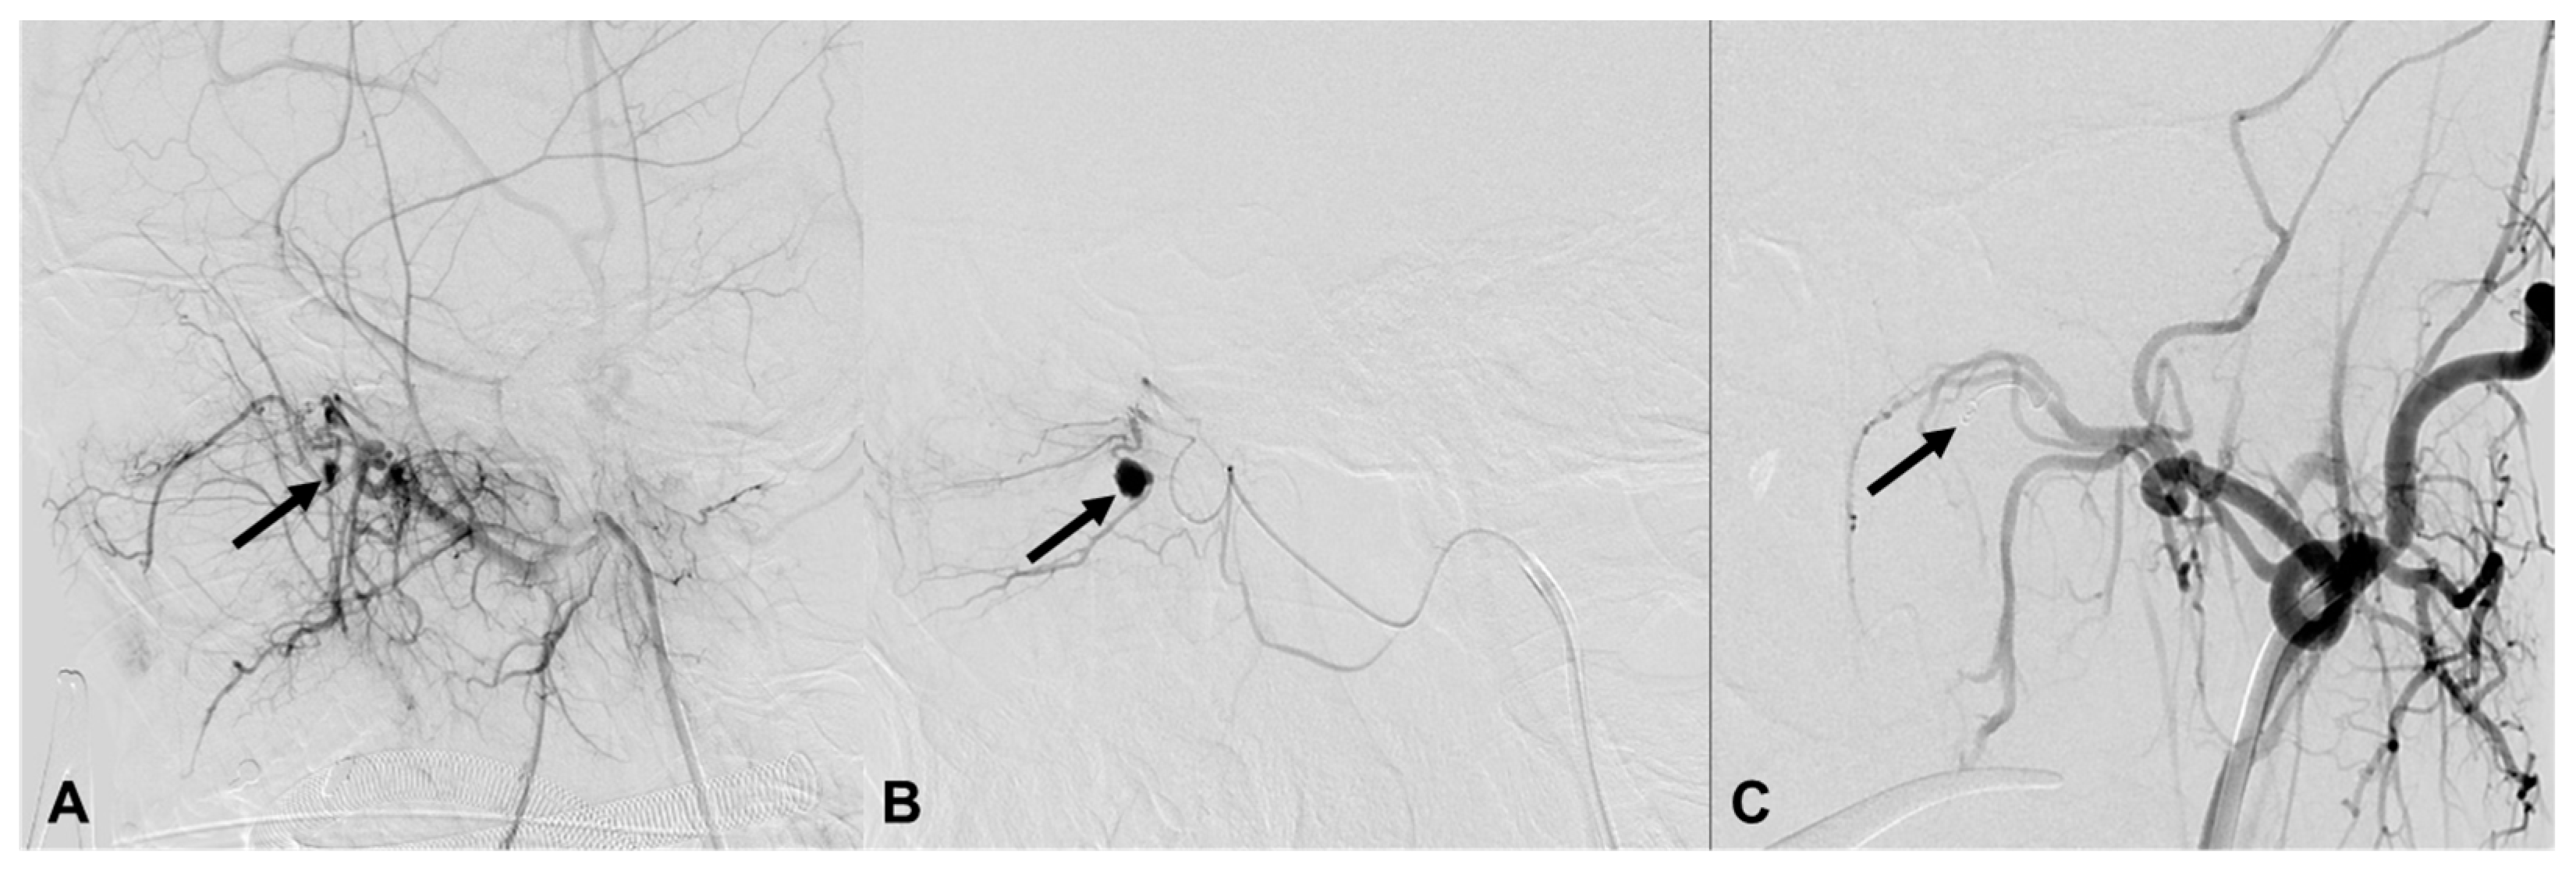

| 3 | 46/M | Fall | Epistaxis and oral bleeding | Le fort II fracture | EV, L IMA branch | Coil | Stable 260 d F/U |

| 4 | 57/M | Fall | Bleeding | Facial and sphenoid bone fracture | EV, L IMA branch | Particle | Stable 4 d F/U |

| 5 | 39/M | Fall | Epistaxis | Facial and sphenoid bone fracture | EV, R IMA branch EV, R cavernous ICA (CCF) | Coil, particle | Stable 39 d F/U |

| 8 | 80/F | TA | Massive oral bleeding | Le fort II fracture | EV, L IMA branch EV, both facial | Particle, coil | Stable 651 d F/U |

| 9 | 61/M | TA | Epistaxis | Le fort II fracture | EV, L IMA branch | Coil | Stable 548 d F/U |